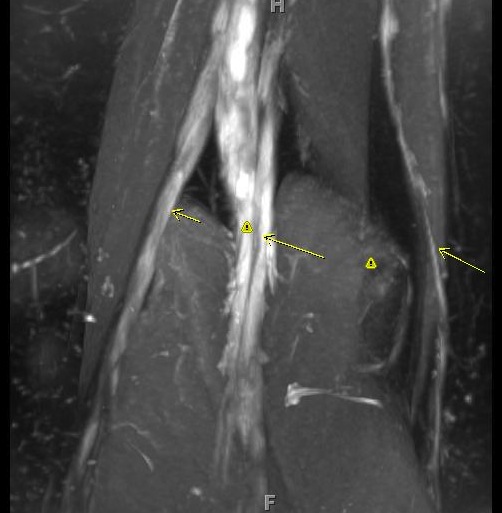

Figure 1 for case Charcot Marie Tooth Type 1a

Figure 1